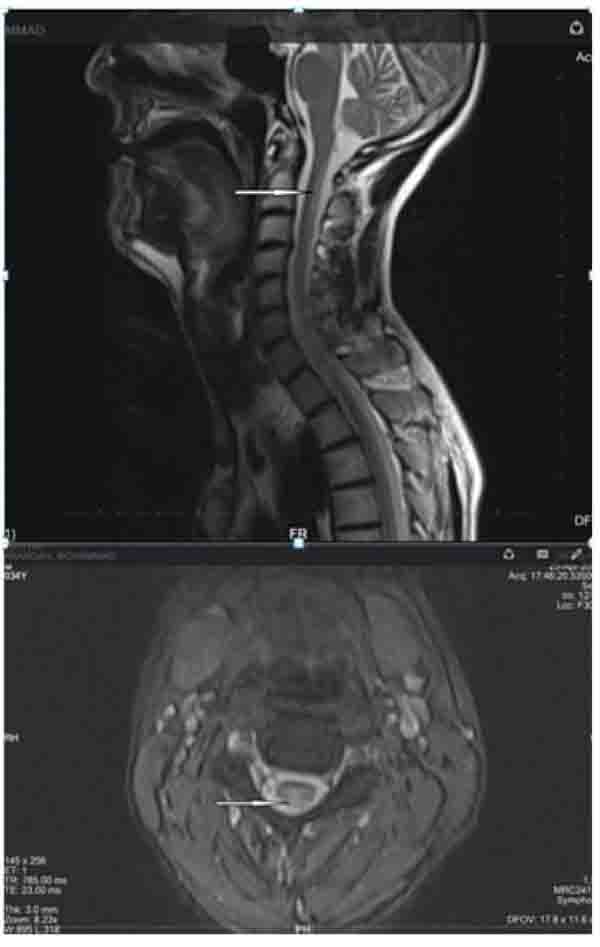

Positive points of our evaluation were: hyper intensity of posterior column in spinal MRI Fig. (3), hyper homocysteinemia (52 micromol/lit, Normal range < 15 micromol/lit), B12 deficiency (pretreatment level 195pgr/ml, Normal range 200-900 pgr/ml), Iron deficiency and normocytic anemia. Peripapillary OCT showed temporal atrophy of optic disc Fig. (4a,b). Perimetry also showed a small paracentral scotoma in the patient’s visual field Fig. (5a,b).

In our case, we confronted two ophthalmological problems: the first was neurotrophic keratopathy and the second was optic neuropathy. The patient had some neurological problems like ataxia, limbal parasthesia and lethargy. Based on this problem list we suspected vitamin B12 deficiency. In addition, para clinic findings showed positive points like spinal MRI with hyper intensity in the posterior column, hyper homocysteinemia, iron deficiency and normocytic anemia. Lower than normal levels of blood B12 were detected and after starting 1000mg/d B12 for the patient, his dramatic response regarding the neurologic signs and keratopathy after 3 weeks confirmed our diagnosis.